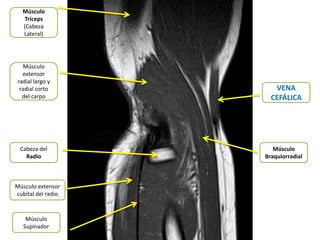

Músculo

Tríceps

(Cabeza

Lateral)

extensor

radial largo y

radial corto          VENA

del carpo           CEFÁLICA

Cabeza del            Músculo

Radio            Braquiorradial

Músculo extensor

cubital del radio

Supinador